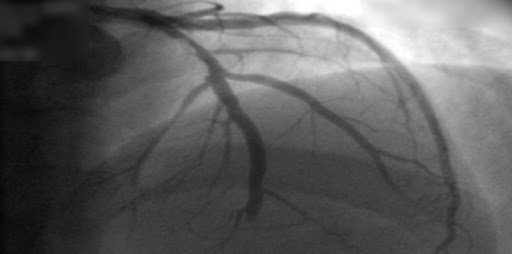

Tomografía computada versus angiografía invasiva en la angina de pecho estable

En los pacientes remitidos para cateterismo coronario por dolor torácico estable y con probabilidad intermedia de enfermedad coronaria antes de la prueba, la evaluación inicial por tomografía computada tuvo un riesgo de eventos cardiovasculares mayores similar a los de la evaluación invasiva, pero una menor frecuencia de complicaciones mayores relacionadas con el procedimiento. New England Journal of Medicine, 28 de abril de 2022.